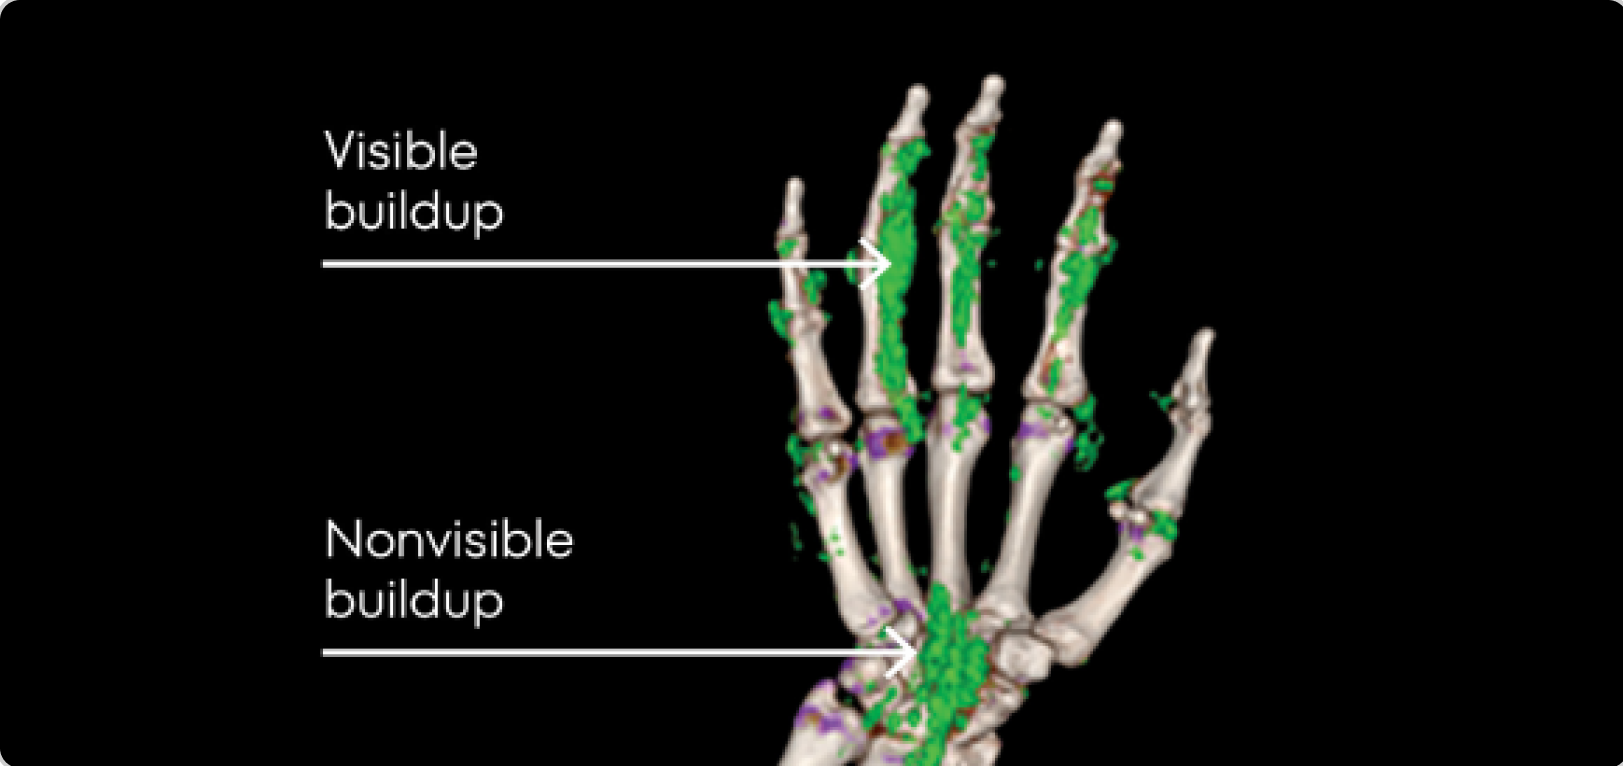

Dual Energy CT scan of hand showing visible and nonvisible buildup in gout patient

DECT OF URATE BUILDUP

DECT image courtesy of Dr. Jurgen Rech. Green areas indicate urate crystal buildup.

DECT, dual-energy computed tomography.

KRYSTEXXA is not indicated for treatment of pain.

Up to 75% of the urate burden may not be detected upon physical examination3